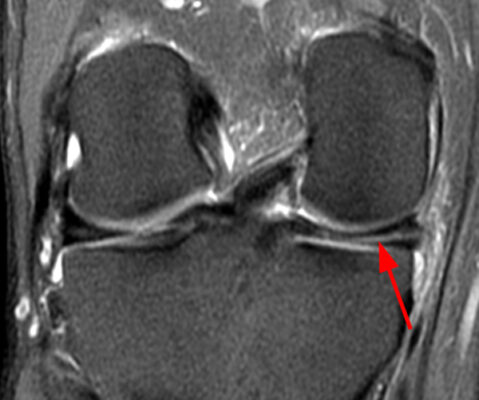

Chụp cộng hưởng từ (MRI)

Rách sụn chêm trong: độ nhạy 91,4% -93% độ đặc hiệu 81,1% -88%

Rách sụn chêm ngoài: độ nhạy 76% -79% độ đặc hiệu 93,3% -86%.

Dương tính giả có thể gặp ở vết rách ở sừng sau của sụn chêm trong và âm tính giả với vết rách hướng tâm (radial tear).

Các nang dịch có mối tương quan cao với rách do thoái hóa.